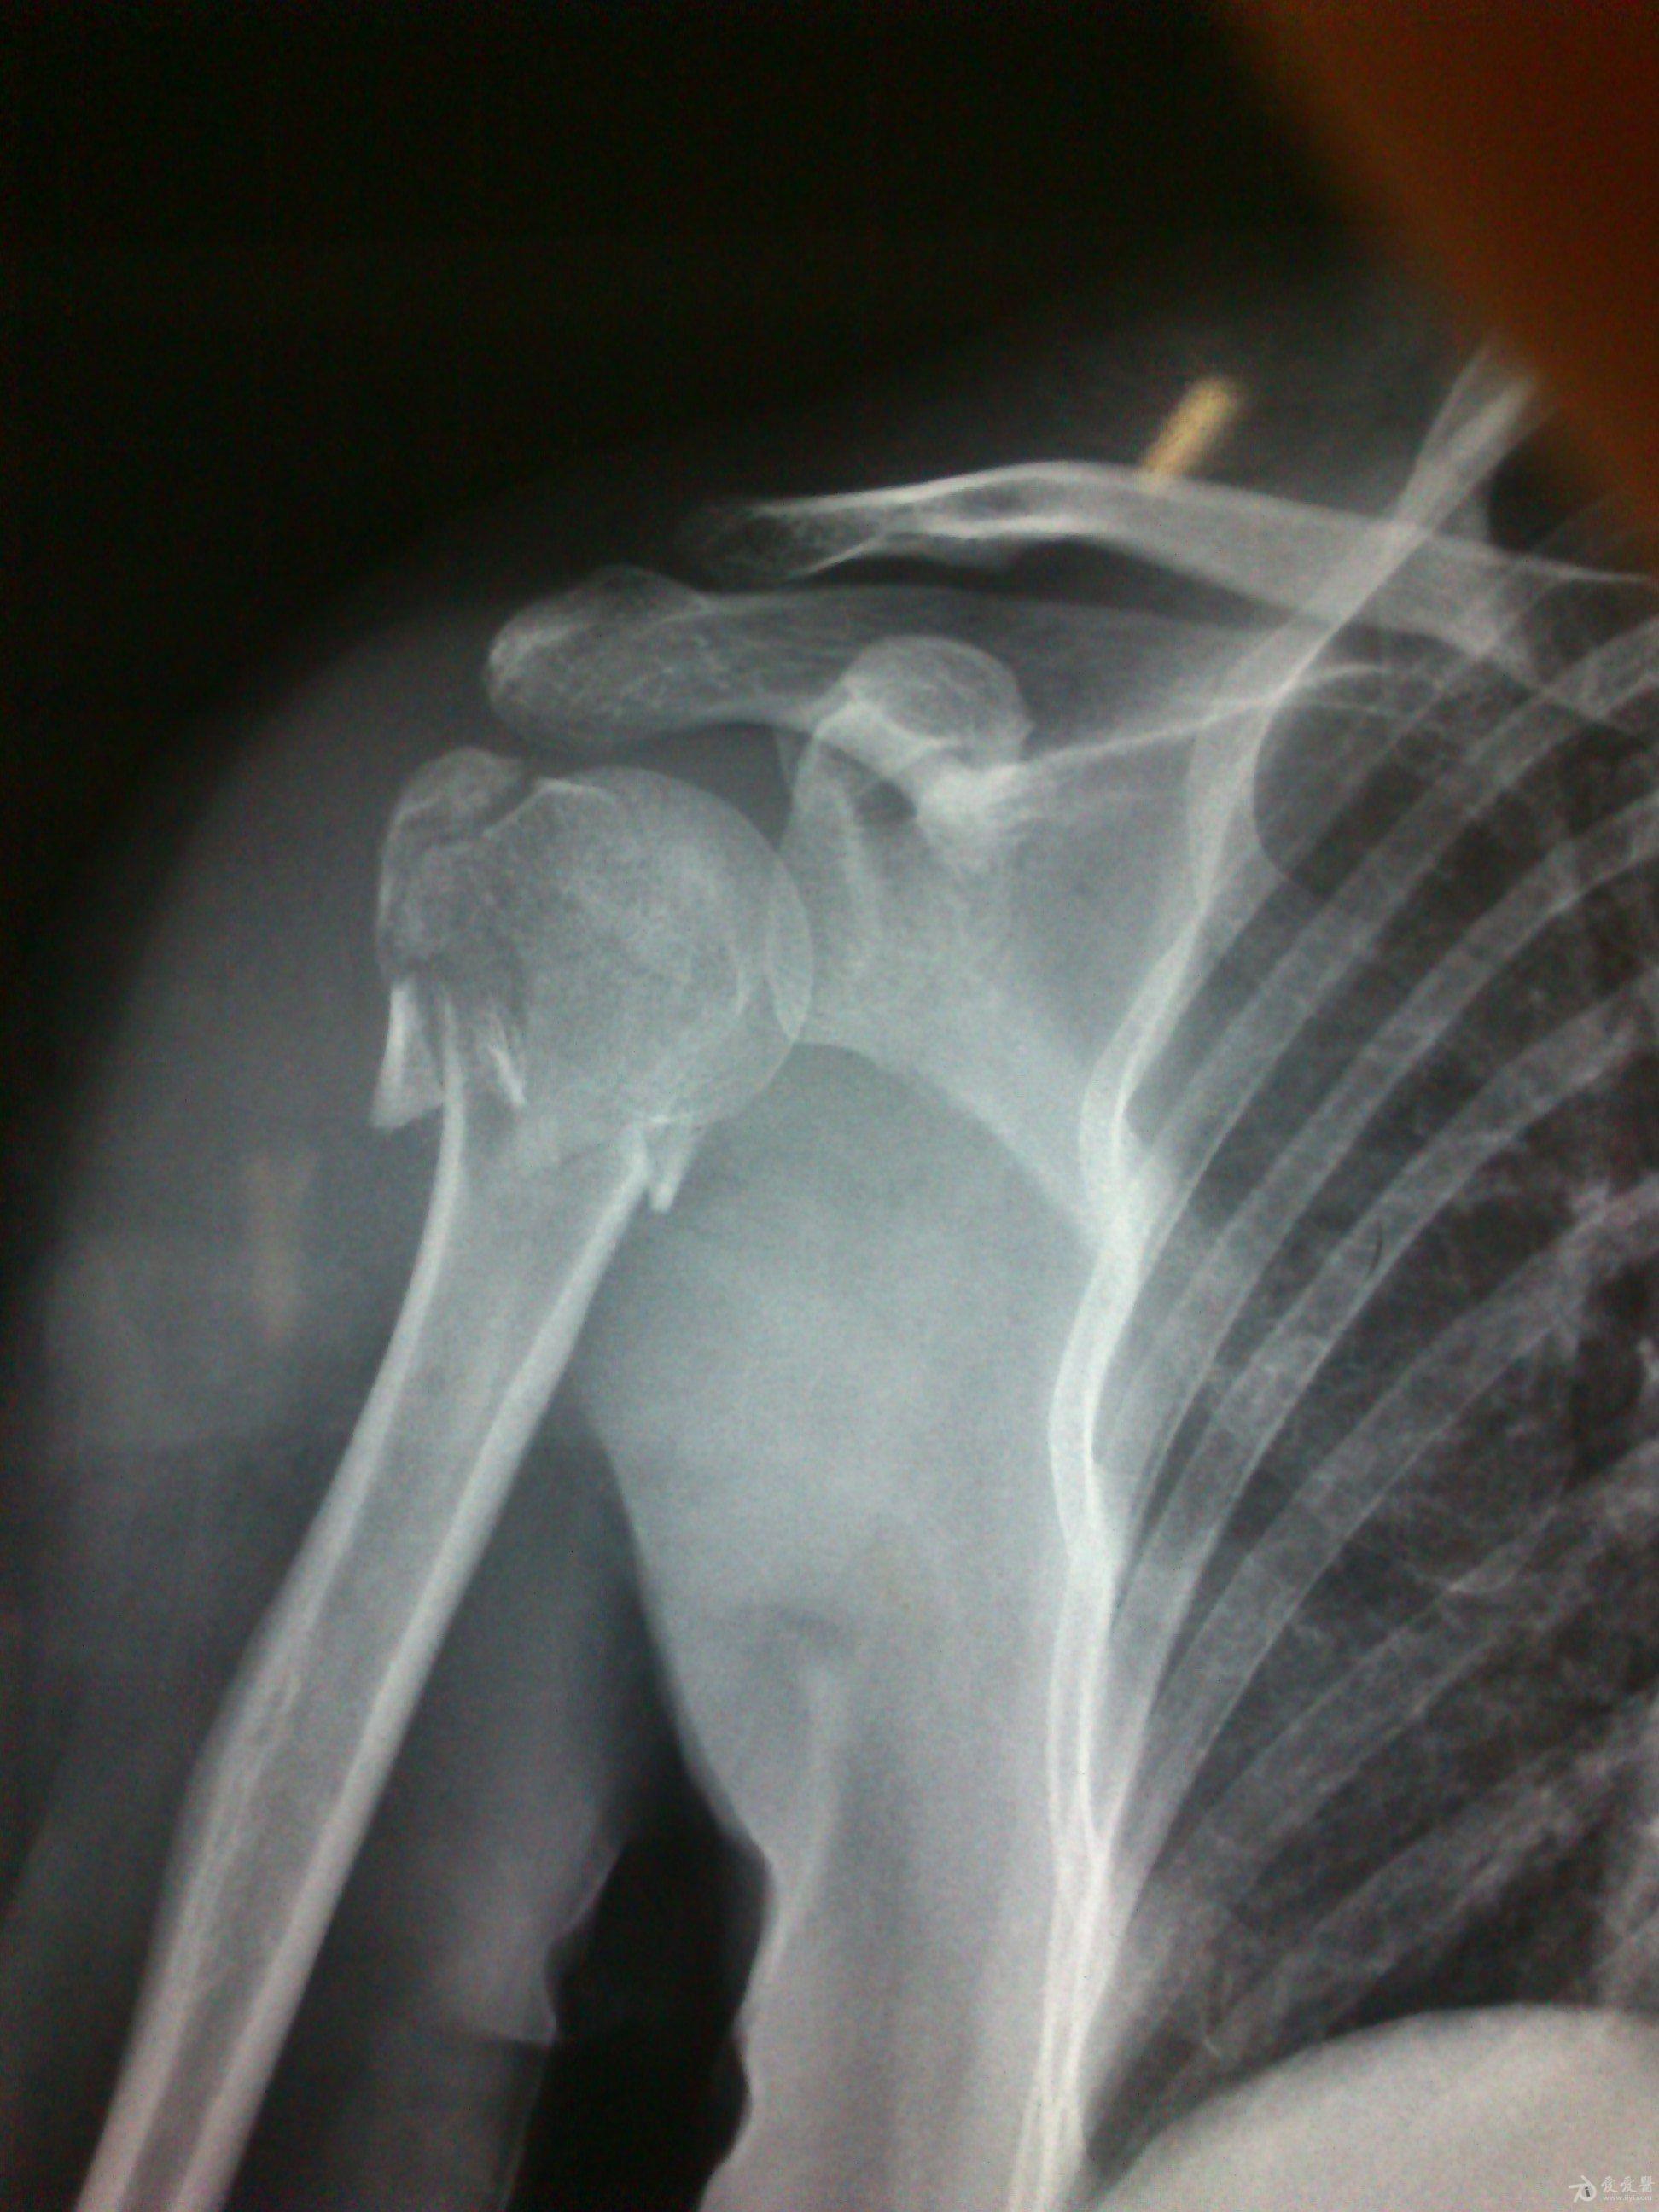

患者:女,51岁,患者因右肱骨外科颈骨折术后右肩疼痛、活动障碍1年余于2012-11-21 14:58:33由步行入院。

病史特点及病情摘要:1、患者女性,51岁。2、患者自诉入院前1年余因右肱骨外科颈骨折在外院行切开复位内固定术,术后右肩关节疼痛、活动受限,一直未予处理,今为明确诊治入院。患者精神、食欲、睡眠尚可。3、既往史、个人史、家族史无特殊。4、入院查体:生命征平稳,心肺腹检查未见异常,NS(-)。专科情况:右上臂近端内侧见一约15cm手术切口疤痕,愈合佳,右肩关节能外展20度,前屈、后伸及旋前、旋后功能障碍,余关节活动好。舌质红,苔薄白,脉实。5、辅助检查:右肩关节正侧位片:右肱骨外科颈骨折内固定术后再骨折伴右肩关节脱位。

诊断:右肱骨外科颈骨折内固定术后再骨折伴右肩关节脱位

诊疗计划:????前两张片是院外术前,中间两张是院外术后,后两张是在我院照。 术前

术前